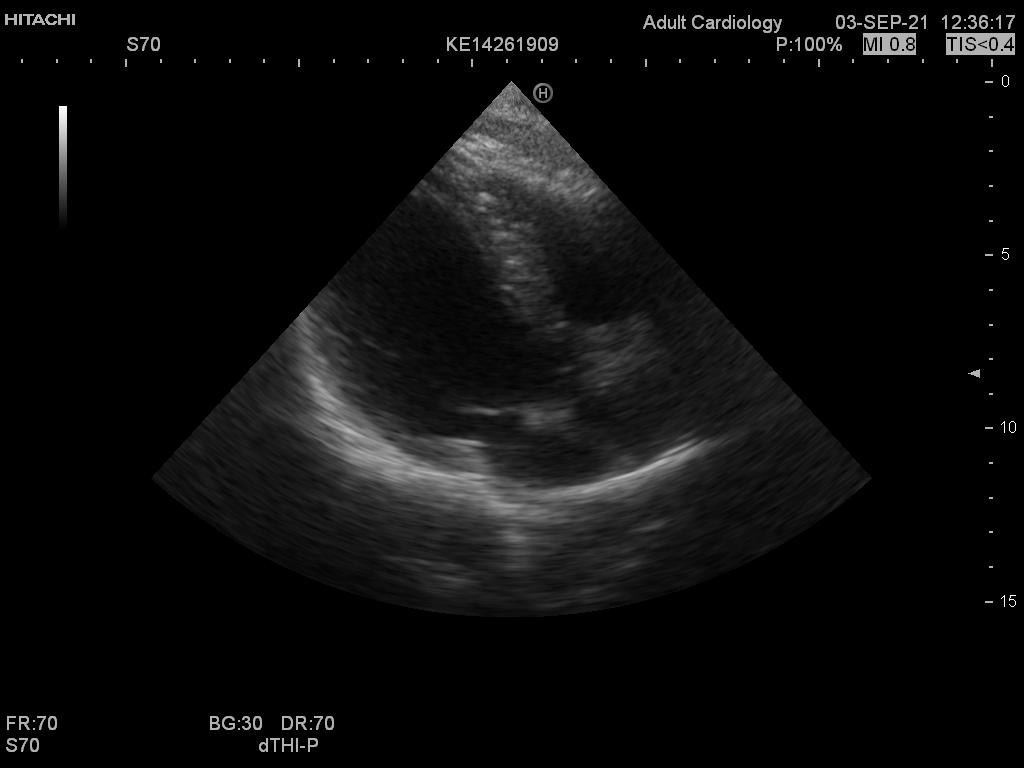

Hitachi EUP-S70 Ref Phased Array – HI VISION

Hitachi Phased Array EUP-S70 Cardio

Intended use

Cardiology and Transcranial

Frequency Range

5 – 1 MHz

Hitachi EUP-S70 Phased Array – HI VISION

Frequency Range: 5 – 1 MHz

Scan Angle: 90° FOV

HI VISION Connector

Hitachi EUP-S70 Phased Array – HI VISION for Cardiology and Transcranial

Compatible with Hitachi Hi Vision systems